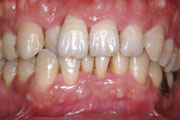

症例1

40歳男性です。主訴は「歯並びを治したい」でしたが、写真のように明らかに歯肉が腫れています。検査の結果、初期の歯周病でした。歯周病治療後矯正治療を行い、欠損していた右上の犬歯はインプラントで補いました。このような場合、歯周病治療をせずに矯正治療を行うと、歯を動かした時にそれを支える骨がなくなり、「きれいに並んだけれど歯はグラグラ」という状態になってしまいます。矯正だけに目を向けるのではなく、お口全体を1つのものととらえ、最も必要なのは治療からすすめていくことが何よりも大切です。